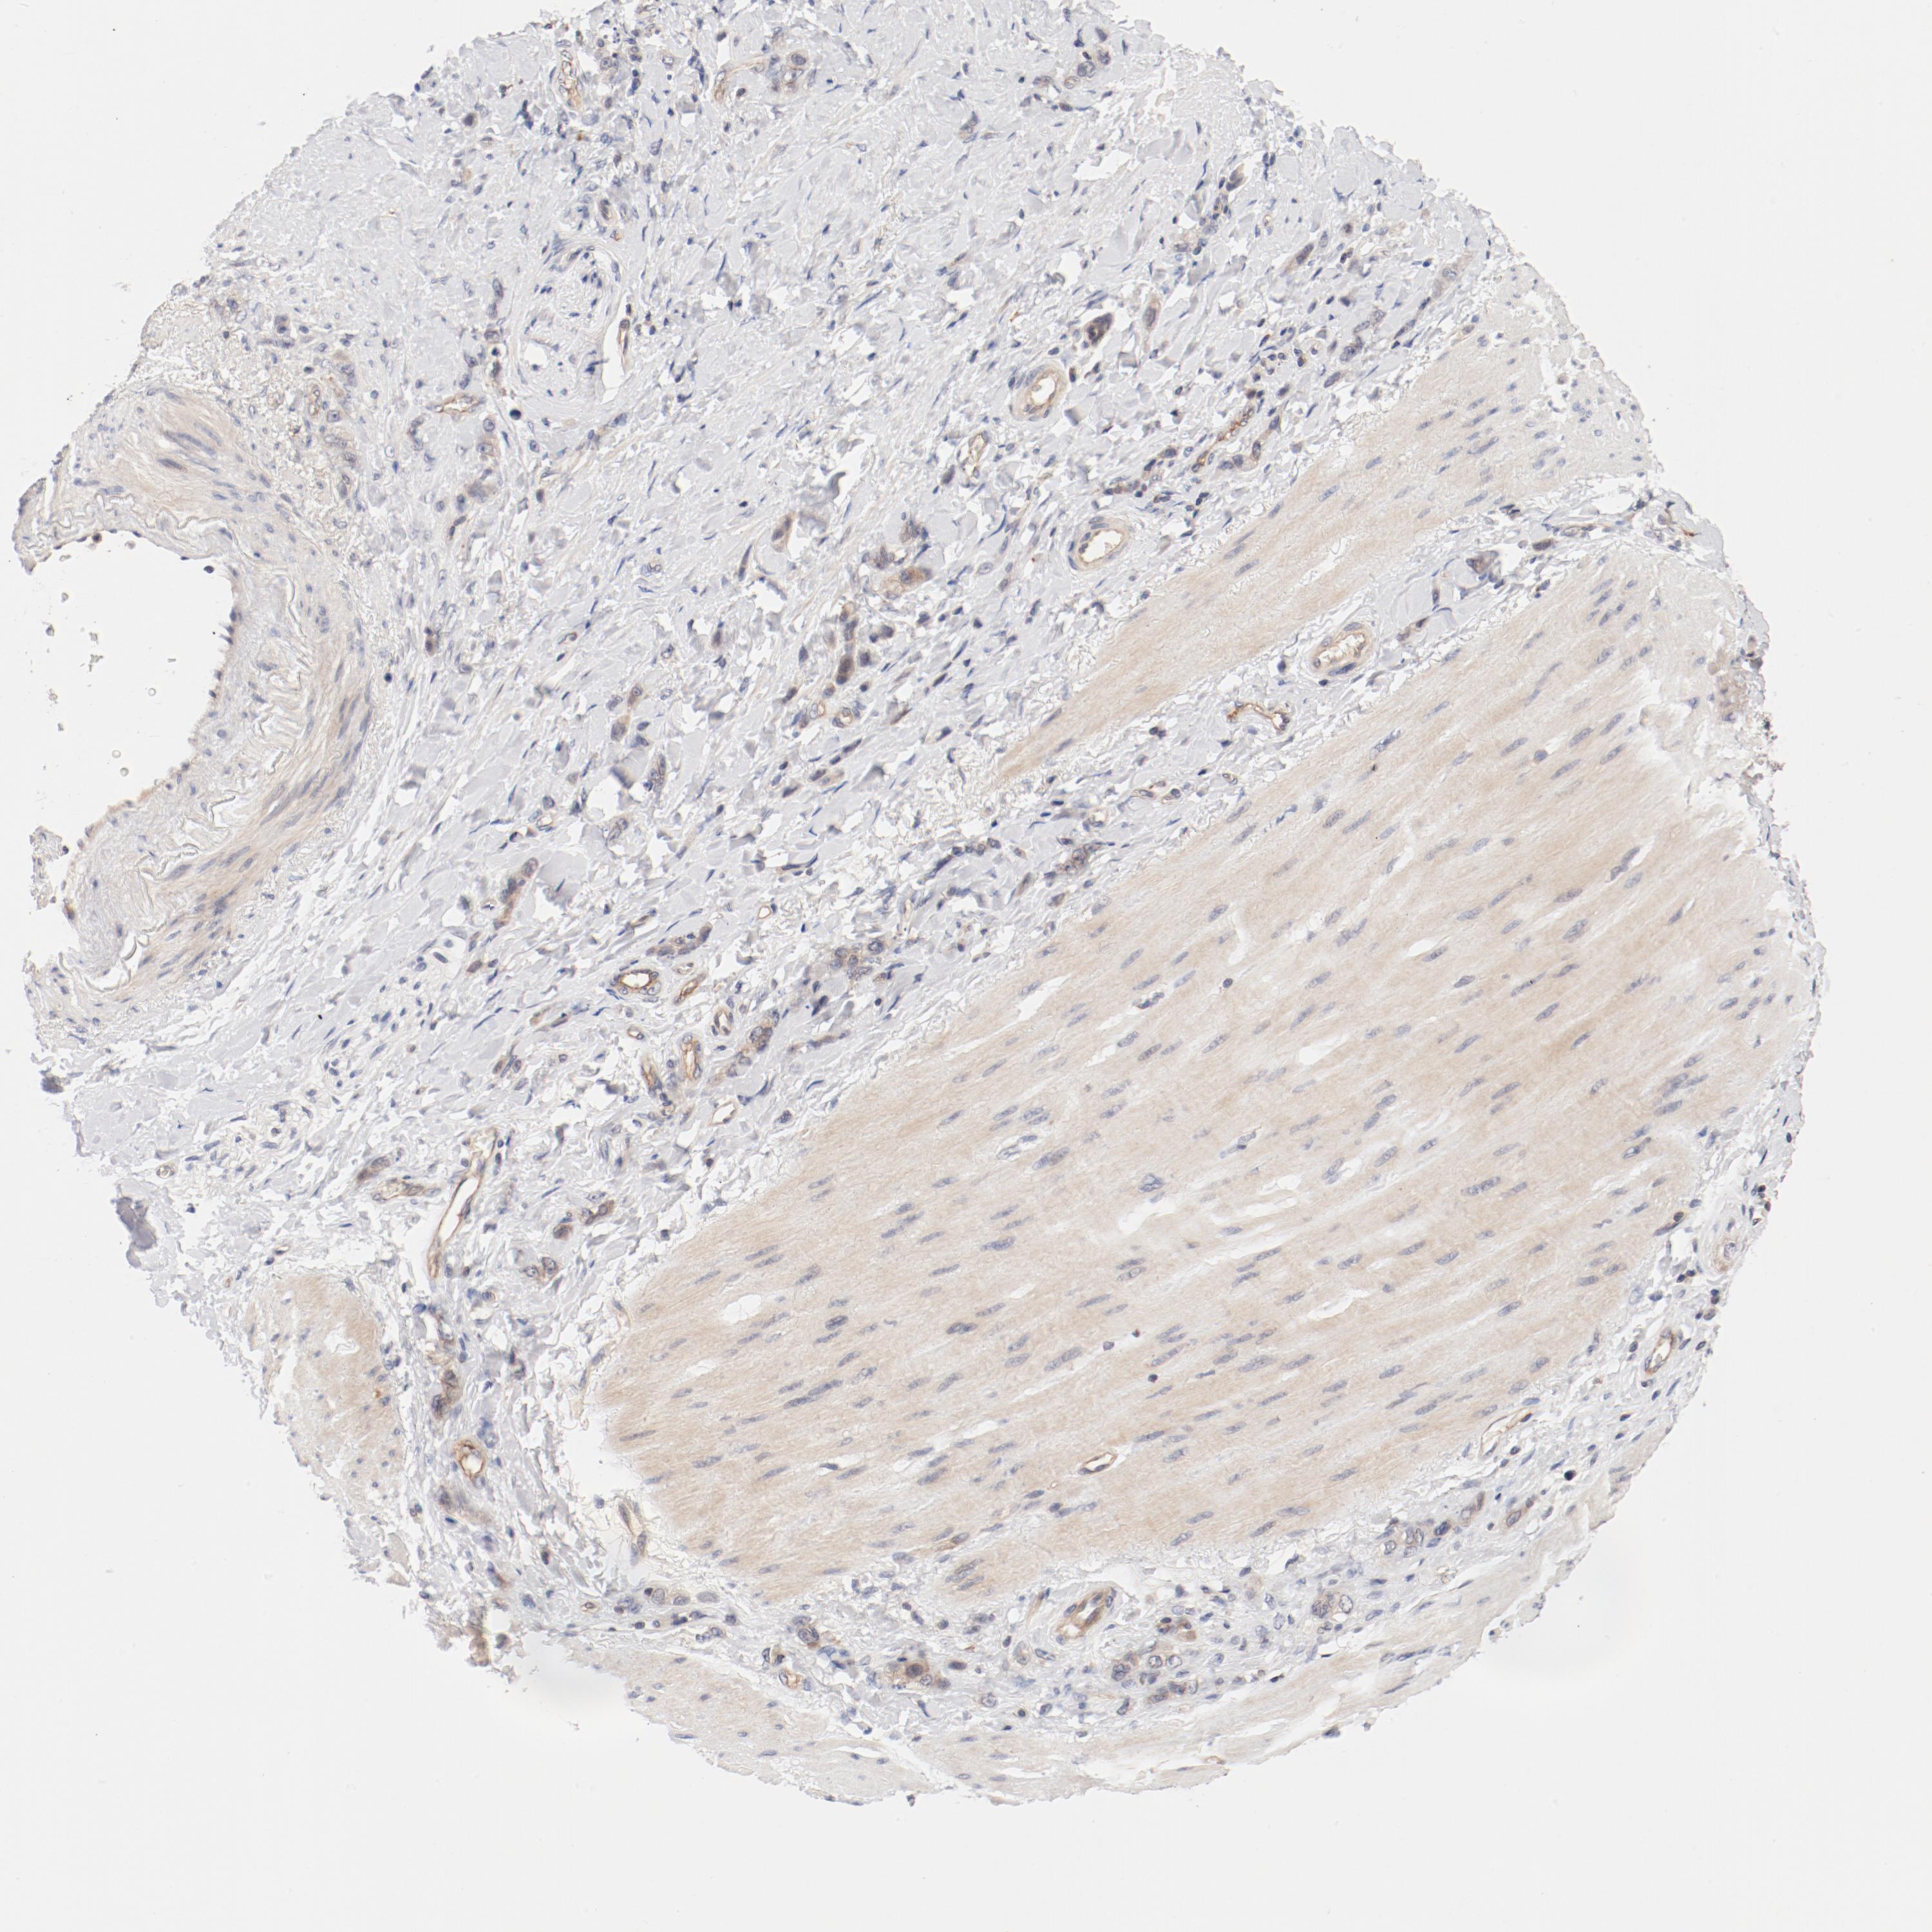

STOMACH CANCER - Protein expressioni

A mouse-over function shows sample information and annotation data. Click on an image to view it in a full screen mode. Samples can be filtered based on level of antibody staining by selecting one or several of the following categories: high, medium, low and not detected. The assay and annotation is described here.

Note that samples used for immunohistochemistry by the Human Protein Atlas do not correspond to samples in the TCGA dataset.

Antibody stainingi

Antibody staining in the annotated cell types in the current human tissue is reported as not detected, low, medium, or high, based on conventional immunohistochemistry profiling in selected tissues. This score is based on the combination of the staining intensity and fraction of stained cells.

Each image is clickable and will lead to virtual microscopy that enables deeper exploration of all samples and also displays staining intensity scores, fraction scores and subcellular localization as well as patient and tissue information for each sample.

Antibody HPA003866

Staining

High

Medium

Low

Not detected

Intensity

Strong

Moderate

Weak

Negative

Quantity

>75%

75%-25%

<25%

None

Location

Nuclear

Cytoplasmic/membranous

Cytoplasmic/membranous,nuclear

Adenocarcinoma, NOS

Adenocarcinoma, High grade